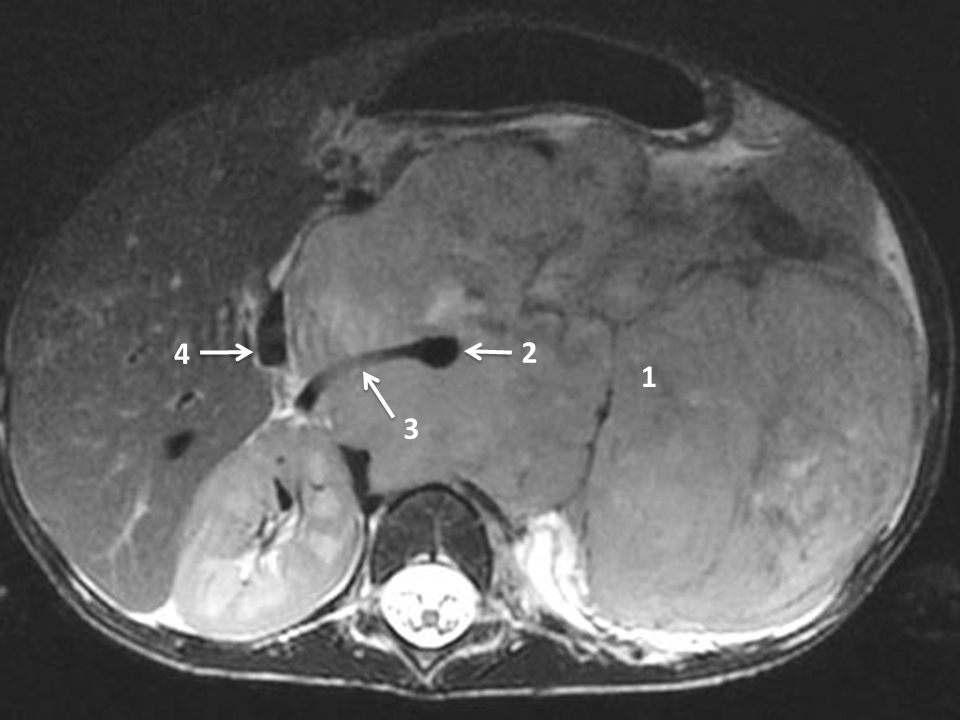

L’IRM ou la TDM (avec injection) précise l’origine anatomique de la tumeur (intra- ou extrarénale), ses rapports avec les organes voisins et avec les principaux vaisseaux. Elle recherche des anomalies locorégionales comme des adénopathies ou une seconde localisation (figures 105.3 et 105.4).

L’IRM est indispensable pour évaluer l’extension intracanalaire et le risque de compression médullaire en cas de neuroblastome paravertébral.

Fig. 105.4 IRM en coupe axiale et pondération T2. Volumineux neuroblastome surrénalien gauche.

La tumeur (1) infiltre le rétropéritoine médian en englobant l’aorte (2), l’artère rénale droite (3) ; la veine cave inférieure est refoulée à droite (4).

Source : CERF, CNEBMN, 2022.